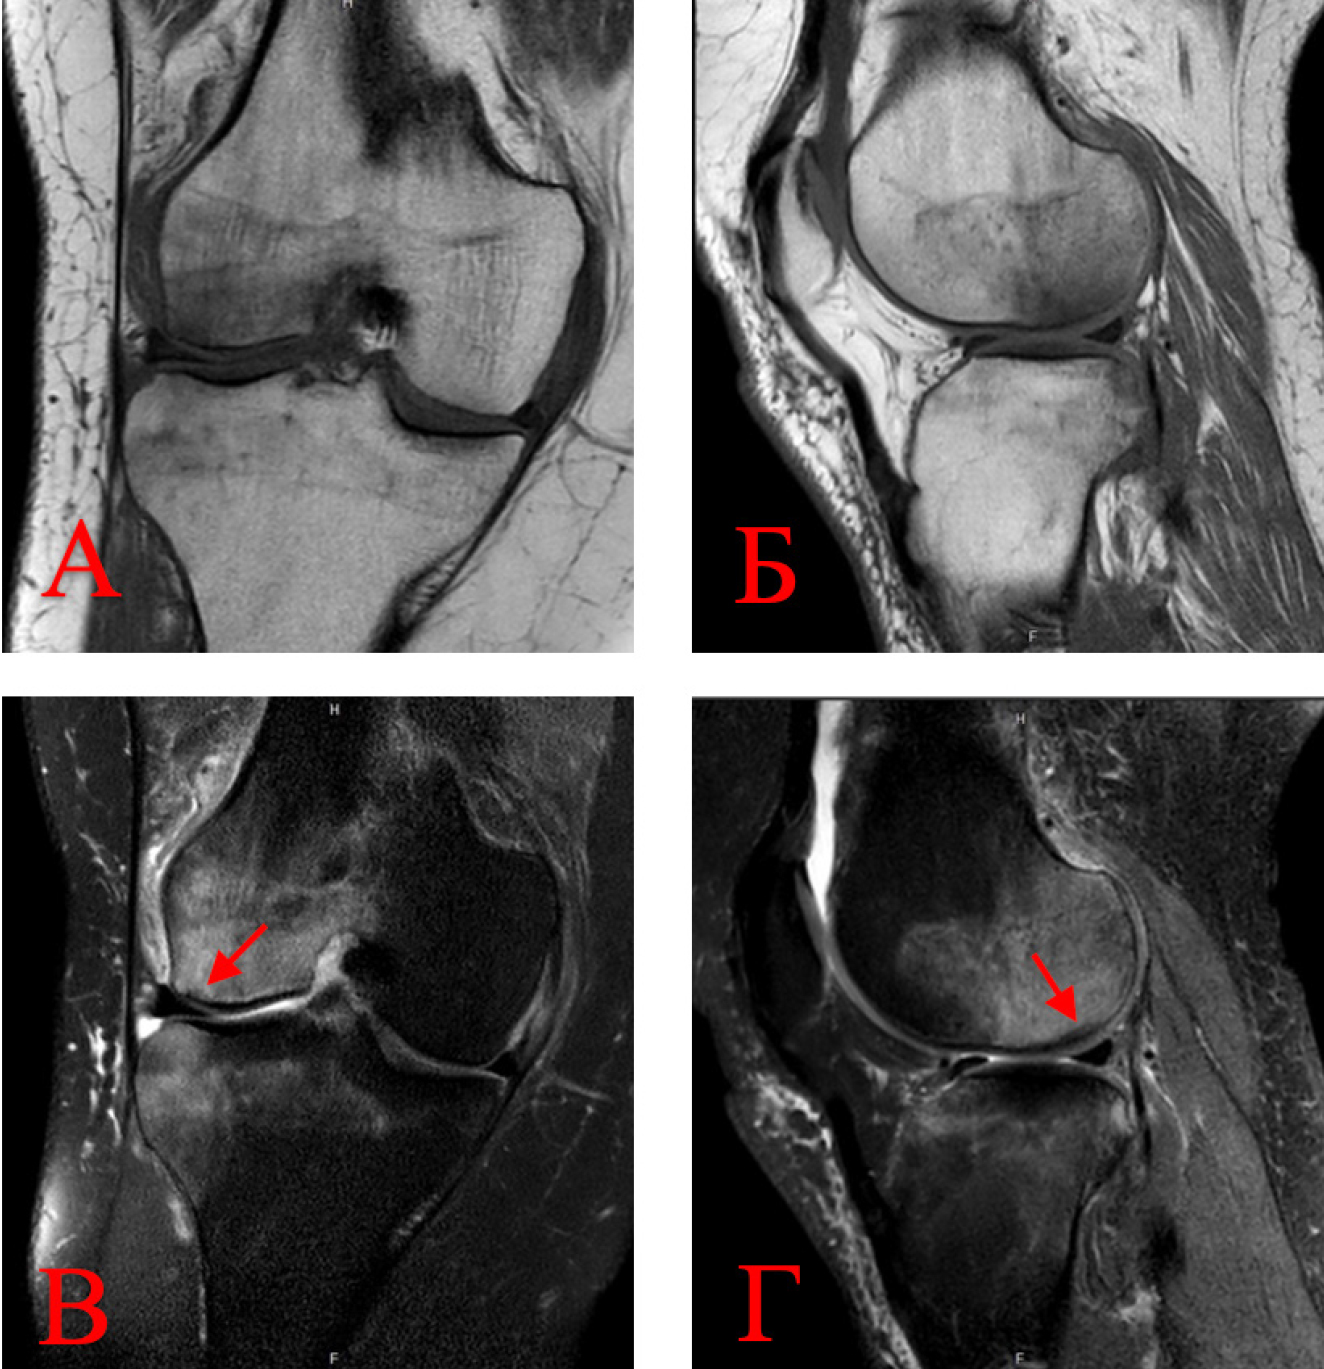

На МРТ коленного сустава были установлены признаки асептического некроза 2-й стадии по классификации Association Research Circulation Osseous (ARCO) и остеоартрита 2-й стадии по классификации Kellgren – Lawrence. При этом на Т2-взвешенных изображениях визуализировалась обширная перифокальная зона неоднородного гиперинтенсивного сигнала за счет отека и ишемии костного мозга в области мыщелков бедренной и большеберцовой костей. На Т1-взвешенных изображениях вышеуказанные участки имели гипоинтенсивный сигнал (рис 1). На Т2-взвешенных изображениях в субхондральной зоне мыщелка бедренной кости прослеживался отграниченный участок гипоинтенсивного сигнала, соответствующий формирующемуся остеонекротическому очагу.

Рис. 1. МРТ-картина асептического некроза и выраженного трабекулярного отека мыщелков бедренной и большеберцовой костей: А, Б – T1-взвешенные изображения; В, Г – T2-взвешенные изображения с подавлением жира. Стрелками обозначен формирующийся остеонекротический очаг